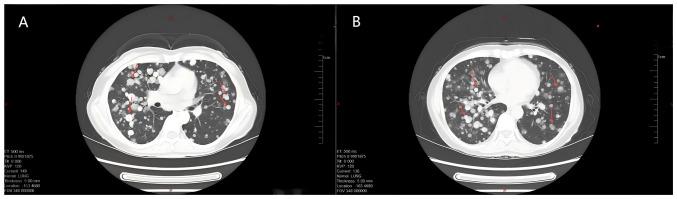

具有非典型组织病理学表现的色素沉着性皮肤病变提示黑色素瘤多发转移的诊断:一例报告。

Pigmented skin lesions with atypical histopathology indicating a diagnosis of multiple metastases of melanoma: A case report.

The present study reports on the case of a middle-aged female patient who presented with a rapidly progressing pigmented skin lesion on the periphery, combined with multiple intracranial, pulmonary, hepatic and skeletal malignancies. The case was not clear in terms of histopathological manifestations and other aspects, which made the diagnosis of melanoma difficult. The present case details the challenges in the diagnostic process, as well as the importance of multidisciplinary comprehensive diagnosis and treatment, aiming to provide a reference for clinicians when dealing with similar complex pigmented skin lesions.

摘要